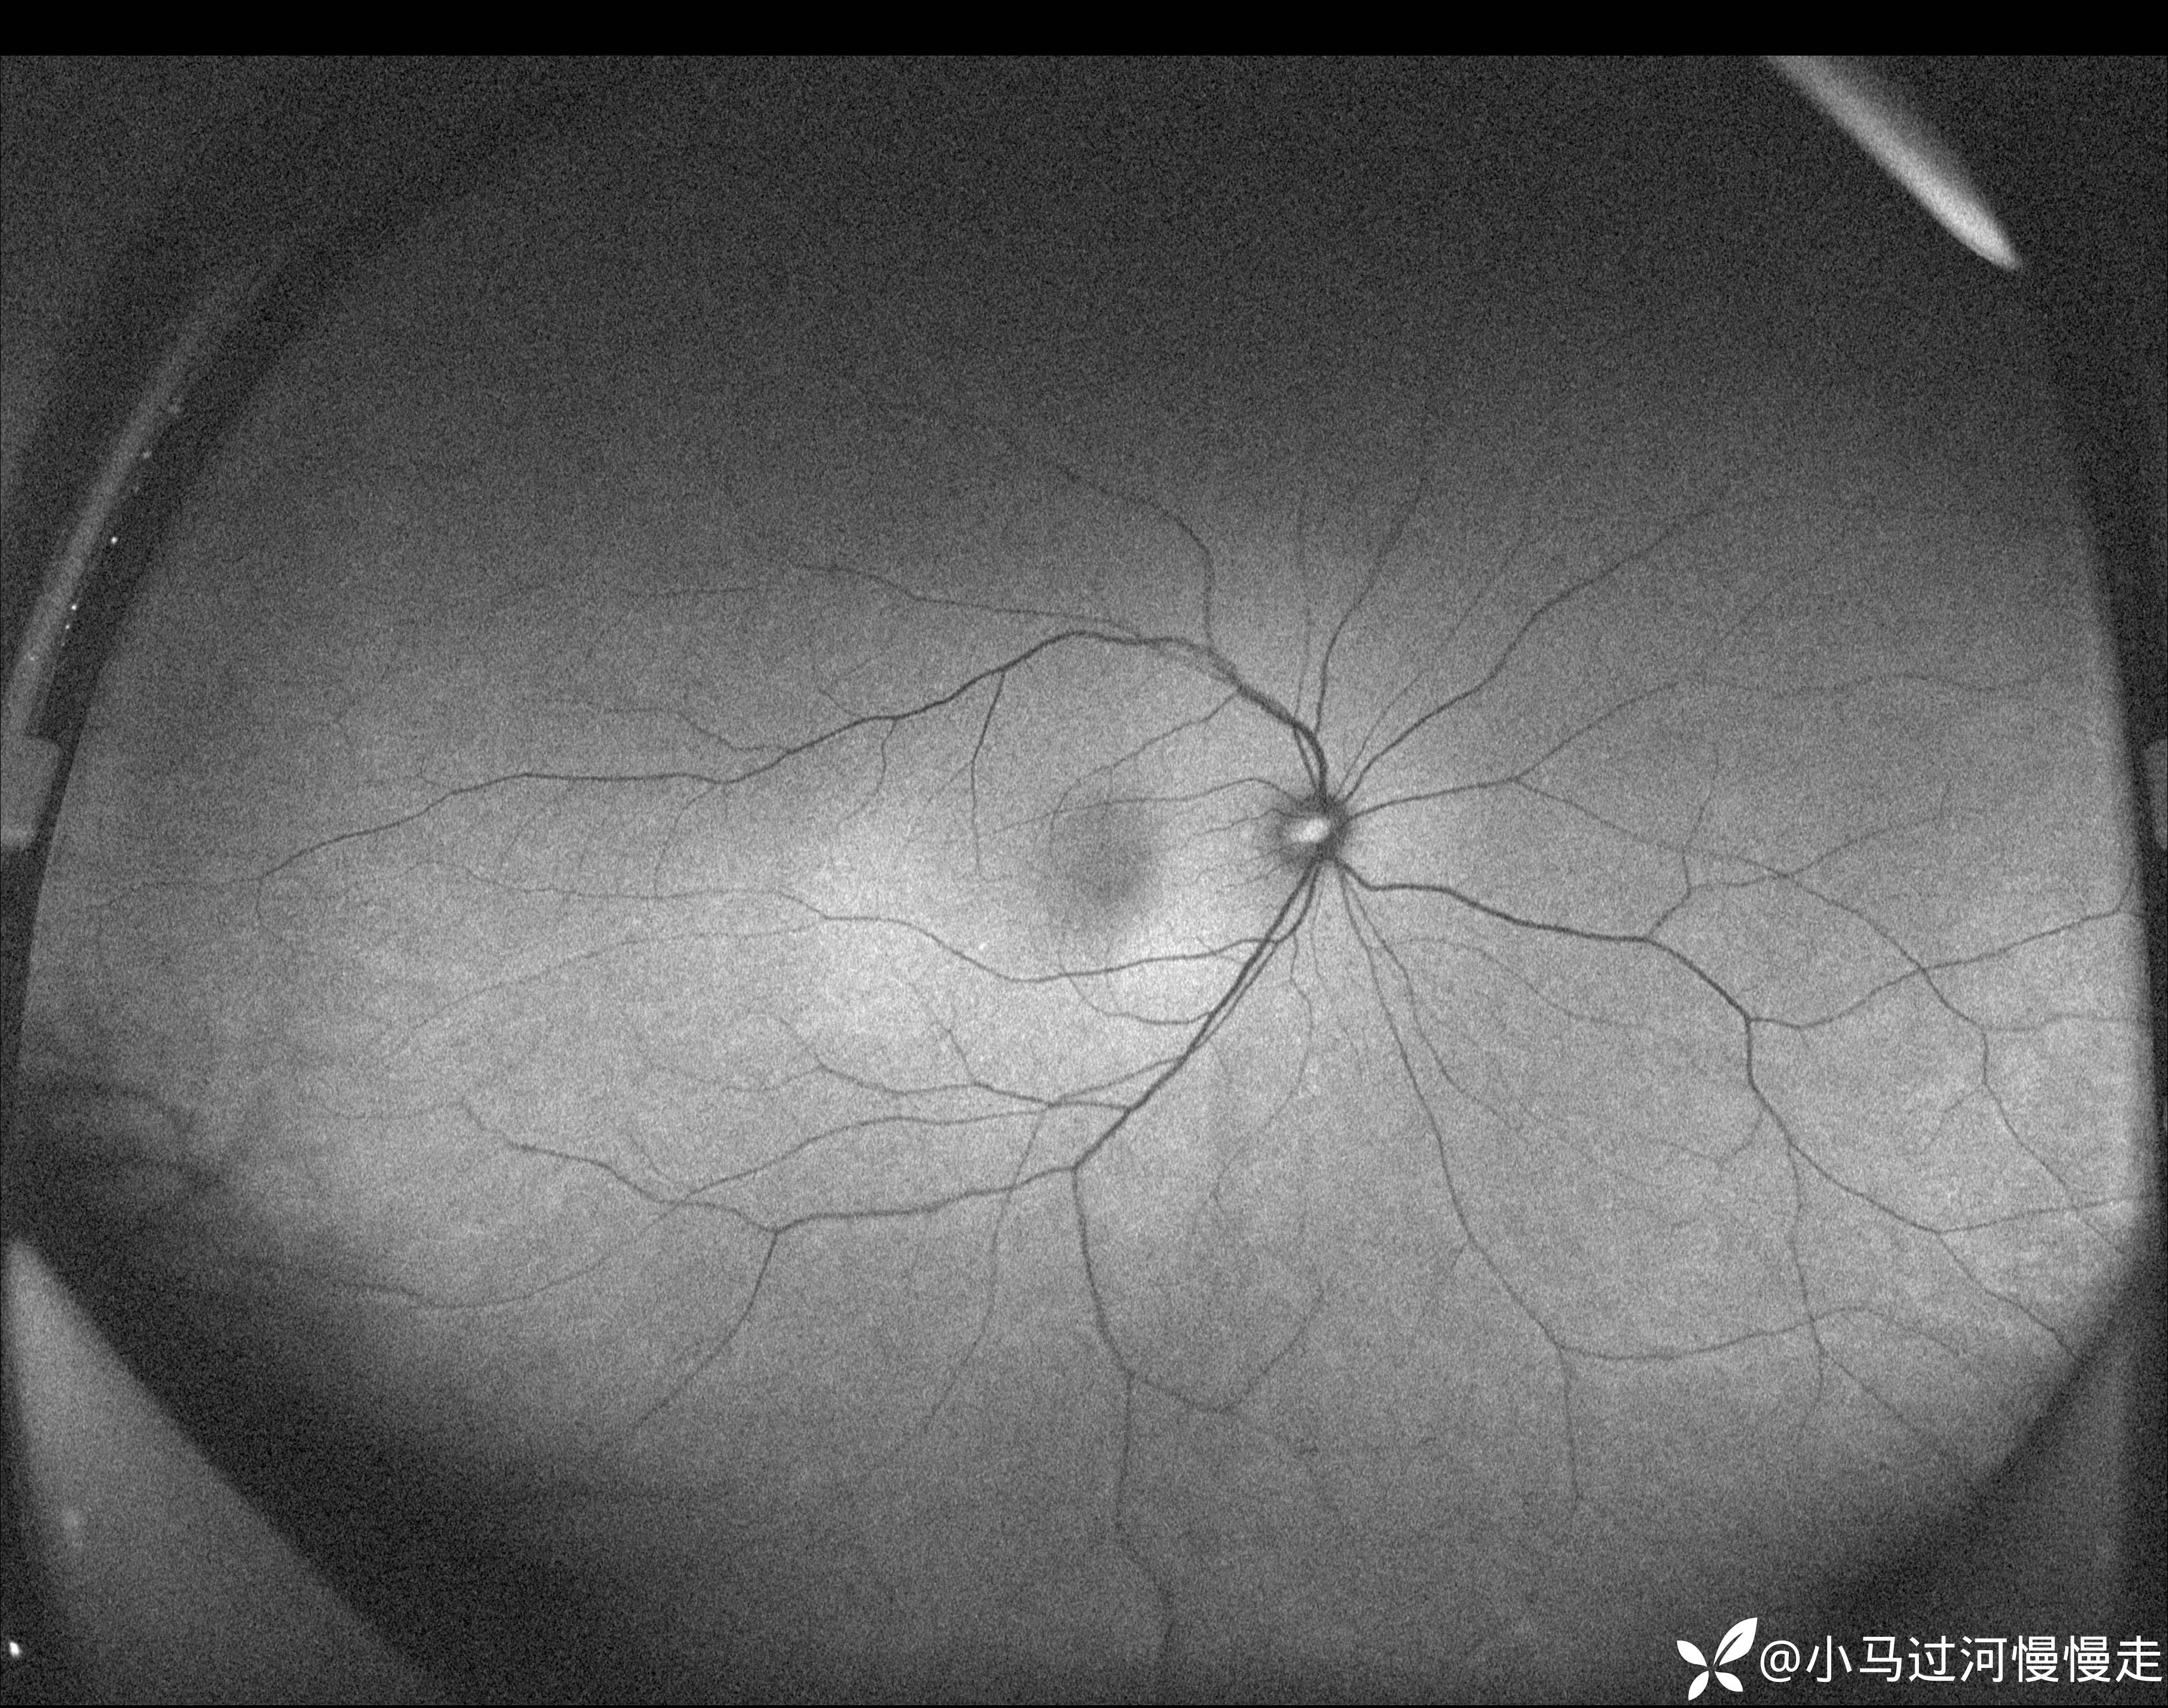

患者是HIV感染者,就诊时外院已经确诊了AIDS。右眼底正常,左眼底表现为霜枝样静脉炎及颞侧"番茄炒蛋"样病变,病变中心可见坏死灶:

当时正在试用视微SSOCT,记录了左眼颞侧病变的影像。